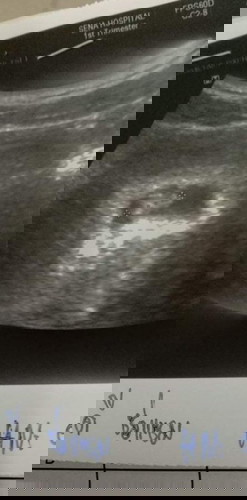

เราท้อง17สัปดาห์กว่าแล้วแต่ท้องยังดูเล็กใครเห็นก็ว่าถ้าไม่บอกก็ไม่รู้ว่าท้องหน้าท้องไม่ค่อยออกเรยจะเห็ชัดก็ตอนอิ่ม น้ำหนักก็ขึ้นมาขีดแล้วก็ลงขีดขึ้นๆลงๆ หรือเพราะเราไม่ได้บำรุง ไม่ได้กินแบบคนท้องคนอื่นที่เคยเห็นเวลาท้องเราเห็นเขากินกันเก่งมาก เราไม่ค่อยอยากกินอะไร #ขอบคุณล่วงหน้านะคะ #ท้องแรกคะ #คุณแม่ๆช่วยแนะนำหน่อยค่ะ